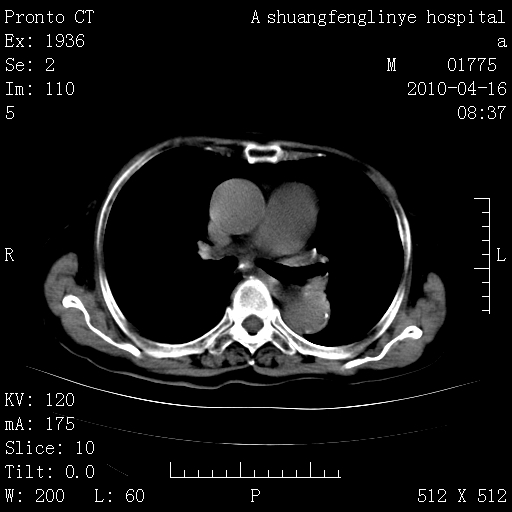

老年肺间质纤维化,肺动脉高压-----肺心病。

典型 夹层动脉瘤。 内膜瓣钙化移位

1)左肺上叶结核(纤维、增殖病灶)。2)冠状动脉及主动脉钙化。

1)左肺上叶结核(纤维、增殖病灶)。2)冠状动脉及主动脉钙化。肺动脉高压